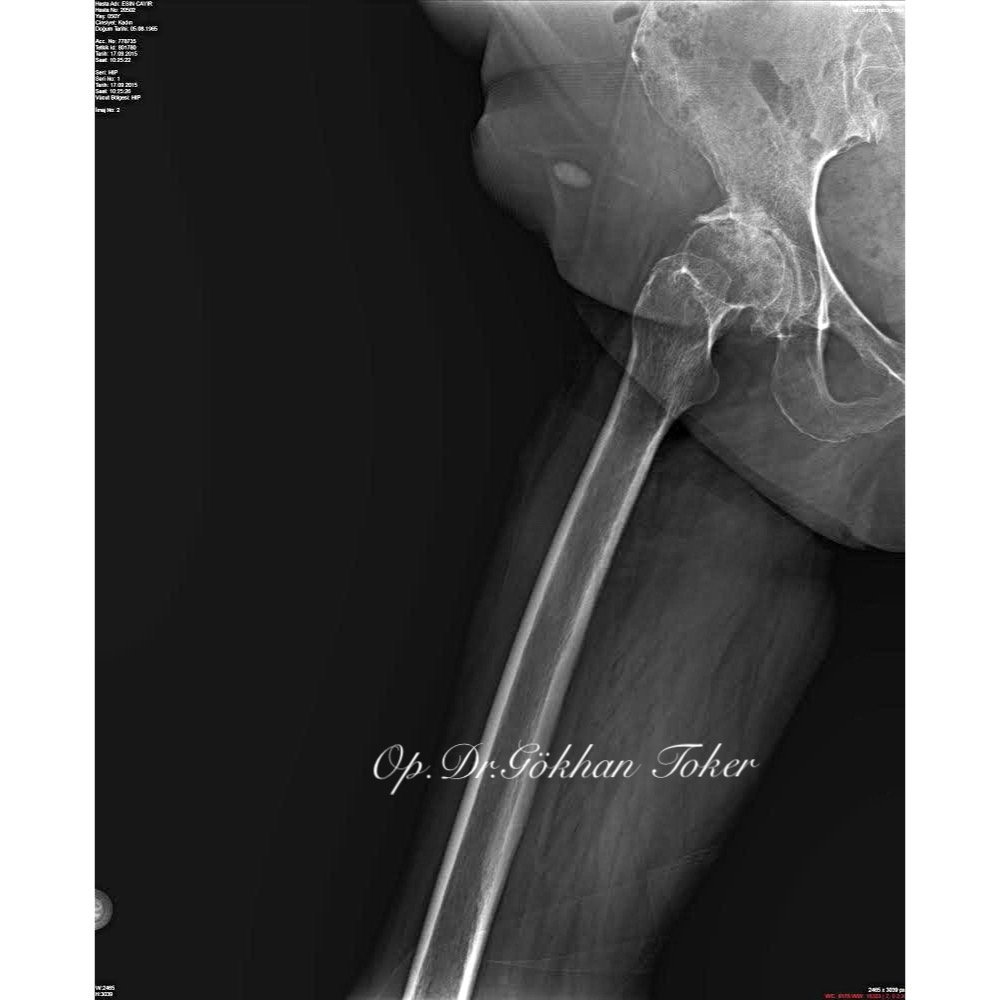

E.C.